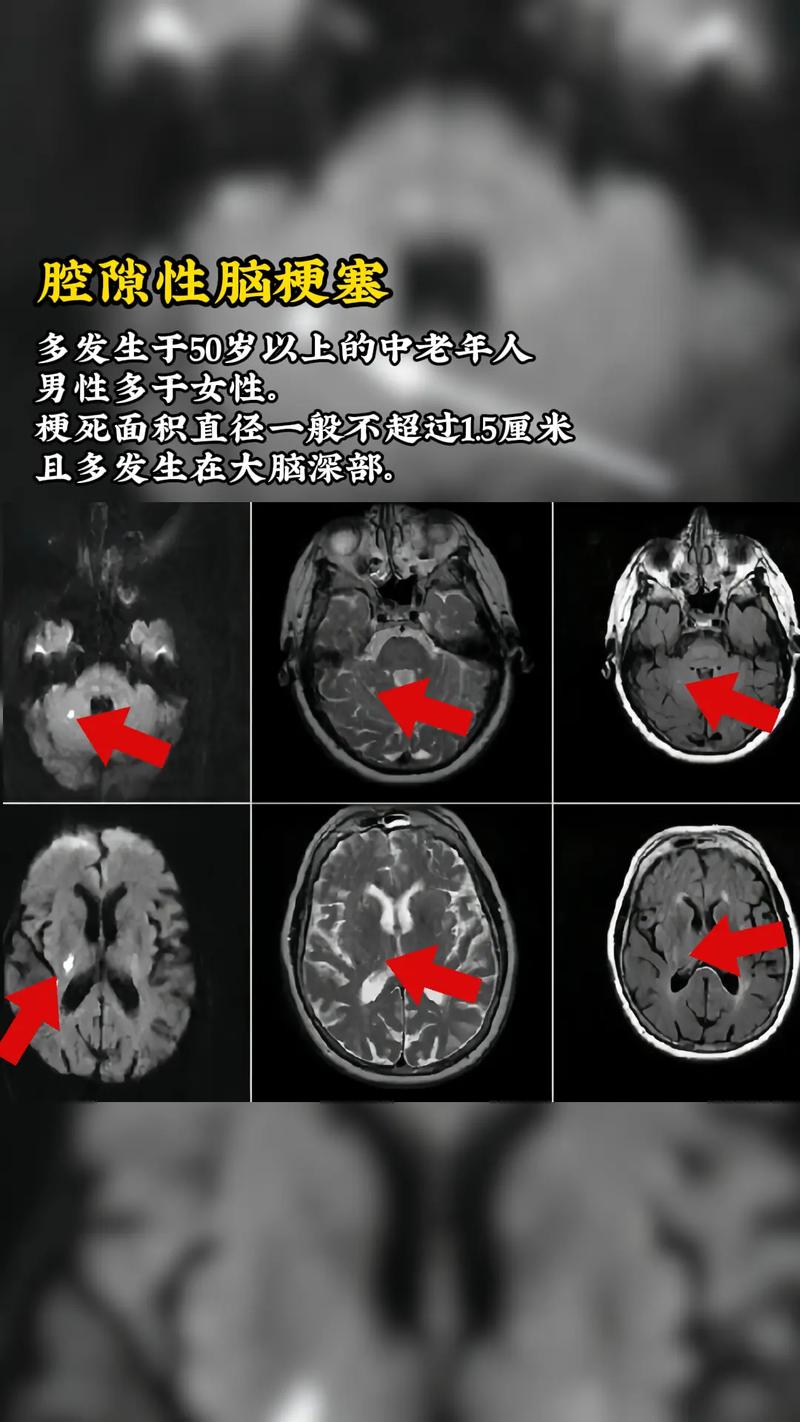

- 因果关系: 一次脑梗塞,就会在脑内留下一个软化灶。“多发性脑梗塞”的病人,其脑部影像(如CT或MRI)上通常就会看到多个脑软化灶。

- 时间关系: 新发生的脑梗塞在影像上可能表现为新鲜的梗死灶(急性期),而旧的脑梗塞则表现为已经形成的软化灶(慢性期),一个病人脑里可能同时存在“新梗塞”和“旧软化灶”。

CT(计算机断层扫描):

- 急性期脑梗塞(几个小时到几天内): 早期可能看不出异常,24小时后才会显示为低密度(发黑)的区域。

- 慢性期脑软化灶: 表现为边界清晰的低密度(发黑)区域,形态不规则,像一个“洞”。

MRI(磁共振成像):

- 急性期脑梗塞: 对早期梗塞非常敏感,几小时内就能发现,表现为T2加权像和FLAIR像上高信号(发白),DWI像上高信号(发白),这是诊断急性脑梗塞的金标准。

- 慢性期脑软化灶: 表现为T1加权像上低信号(发黑),T2加权像和FLAIR像上高信号(发白),其内信号均匀,像脑脊液。